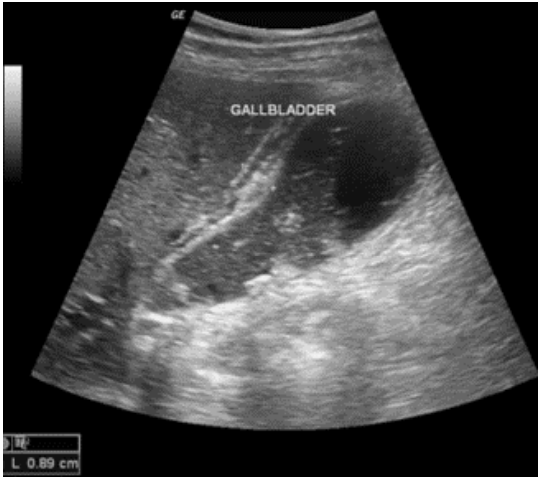

Paciente do sexo feminino, 69 anos, procurou atendimento de urgência referindo, há 1 dia, dor abdominal em faixa superior, febre, náuseas e vômitos. Ao exame físico: dor a palpação do hipocôndrio direito. Leucocitose. Evoluiu sem melhora do quadro clínico após analgesia.

Qual o diagnóstico mais provável?